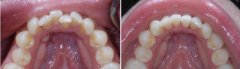

牙齿拥挤要怎么修复?

牙齿拥挤是常见的错合畸形,表现为牙齿拥挤错位排列不齐;而拥挤牙齿的龋及...【详细】

矫正牙齿拥挤需要拔牙吗?

牙齿拥挤是患者内心的一块石头,严重影响外观,还会影响身体健康,很多人因...【详细】